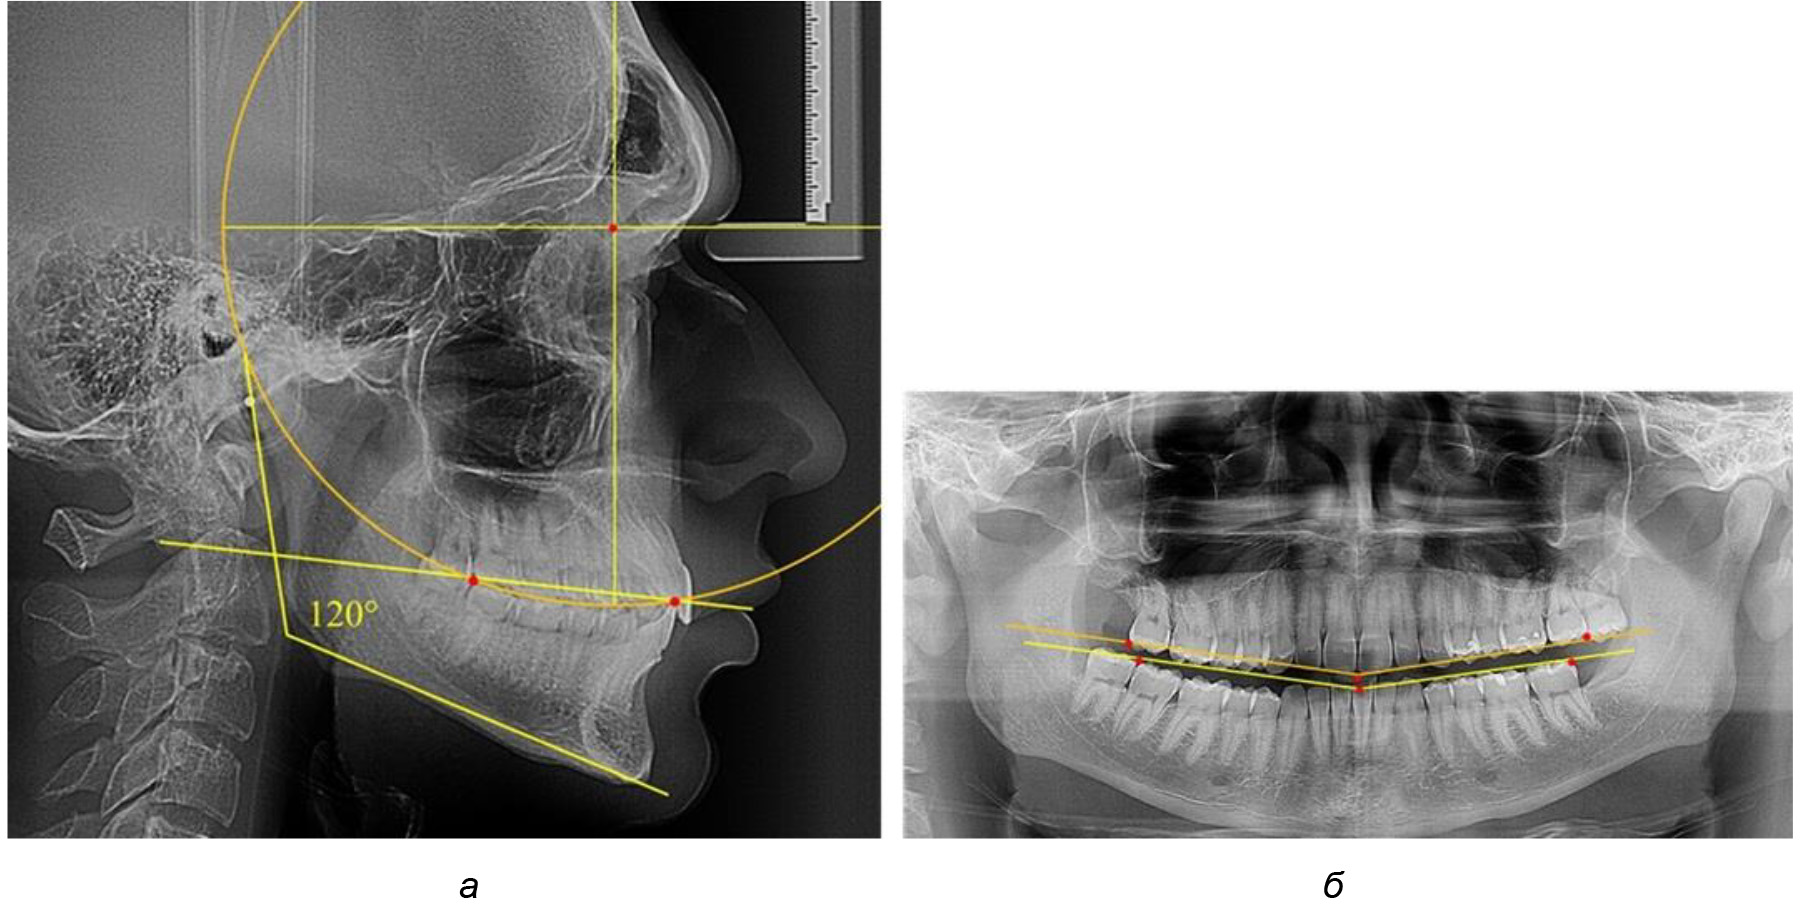

Рис. 2. Особенности кривой Spee на ТРГ (а) и ОПТГ (б) у людей с признаками вертикального роста

На рентгенограммах людей 2-й подгруппы (30 человек с нейтральным типом роста) величина угла нижней челюсти в среднем составила (120,34 ± 2,19) ° и характеризовала нейтральный тип нижней челюсти.

Глубина кривой Spee в среднем по 2-й подгруппе составил (3,54 ± 0,58) мм, что было незначительно меньше, чем при анализе аналогичного показателя 1-й подгруппы.

Достоверных различий с показателями, полученными при анализе ТРГ и ОПТГ, нами не отмечено (р ˃ 0,05). Деление величины радиуса круга к длине окклюзионной линии составило 1,612 ± 0,02, что, так же как и в 1-й подгруппе, было близким по значению к числу Фибоначчи (1, 618).